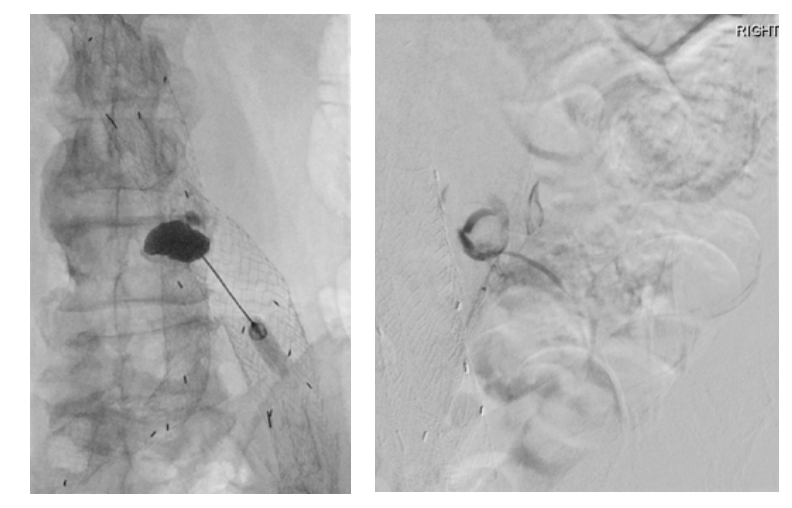

Given the patient’s advanced age and multiple medical co-morbidities, in conjunction with the complexity of his endoleak nidus, the decision was made to utilize advanced navigational software for treatment planning and delivery. The procedure was performed under general anesthesia in the interventional radiology suite. After the patient was secured in a prone position, a cone-beam CT was acquired and multiplanar reconstructions were generated using syngoDynaCT. The pre-intervention CT angiogram dataset was then utilized to estimate the total volume of the endoleak nidus and to identify adjacent vital structures, including the indwelling endograft. The CT angiogram and DynaCT datasets were fused, ultimately creating an overlay of pre-defined regions of interest to be displayed during live 2D fluoroscopy. Lastly, syngo needle guidance software was used to define the ideal needle trajectory (Figure 2). After a skin entry point was identified, a 20-gauge chiba needle was aligned with the integrated laser crosshairs projected onto the patient’s skin. The needle was advanced under direct fluoroscopic guidance, maintaining the x-y coordinates delineated by the navigational software. After gaining sufficient access into the paraspinal soft tissues, the needle guidance software was advanced to display the remaining distance to the target in the z-axis. Once the target was reached, the inner stylet was removed from the needle, and pulsatile blood flow was observed. Extension tubing was connected to the needle hub, and contrast was gently injected under fluoroscopy to confirm positioning within the aneurysm sac. A digital subtraction angiogram was performed, demonstrating opacification of at least one prominent lumbar artery at the L3-L4 level (Figure 3). The needle was flushed with normal saline followed by DMSO (dimethyl-sulfoxide) in preparation for embolization using the Onyx, (Medtronic, Minneapolis, Minnesota), a liquid embolic agent consisting of ethylene vinyl alcohol (EVOH) co-polymer, DMSO, and micronized tantalum powder. Using the integrated overlay showing anticipated nidus volume, a combination of Onyx 18 and Onyx 34 were slowly injected under direct fluoroscopic visualization until the anticipated volume had been reached and the complex iliolumbar collateral network was opacified. In total, 5.6 mL of Onyx 18 (6% EVOH) and 1.4 mL of Onyx 34 (8% EVOH) were administered. The needle was removed, and a final cone-beam CT was obtained to document the extent of the embolic cast (Figure 4).